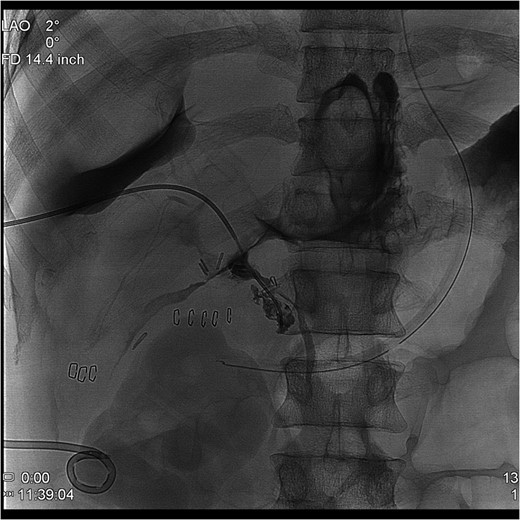

The PTC study confirmed the presence of a completely transected duct, and, fortunately, the ductal injury was traversed with a wire with entry into the distal ductal orifice and into the duodenum (Figs 4–6). Following the procedure, the patient was taken directly to the operating room for open surgical repair.

Percutaneous Transhepatic Cholangiogram with proximal contrast extravasation. Note adjacent surgical clips.